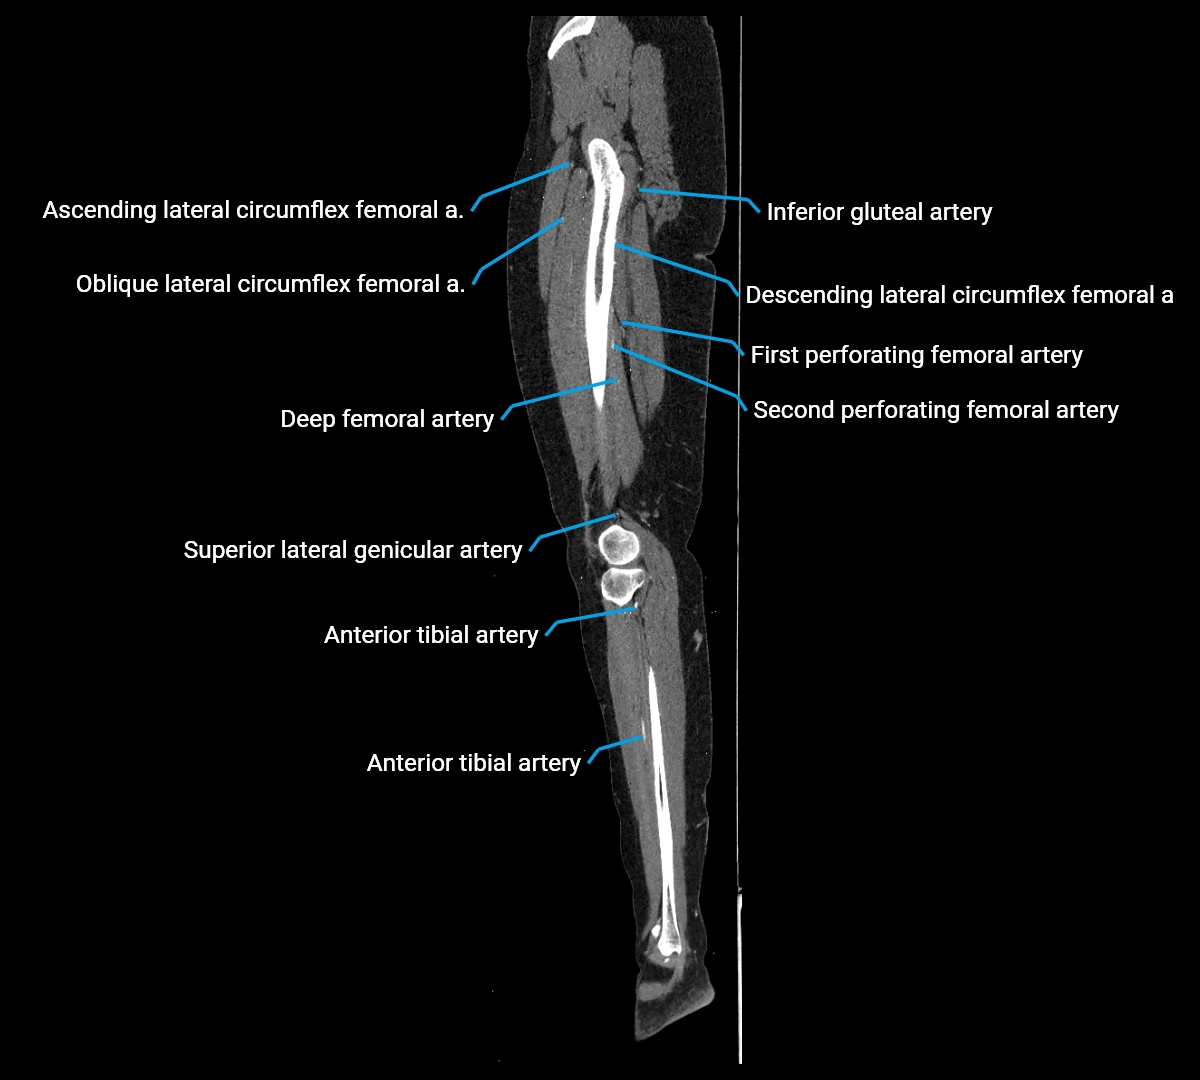

CT images

image